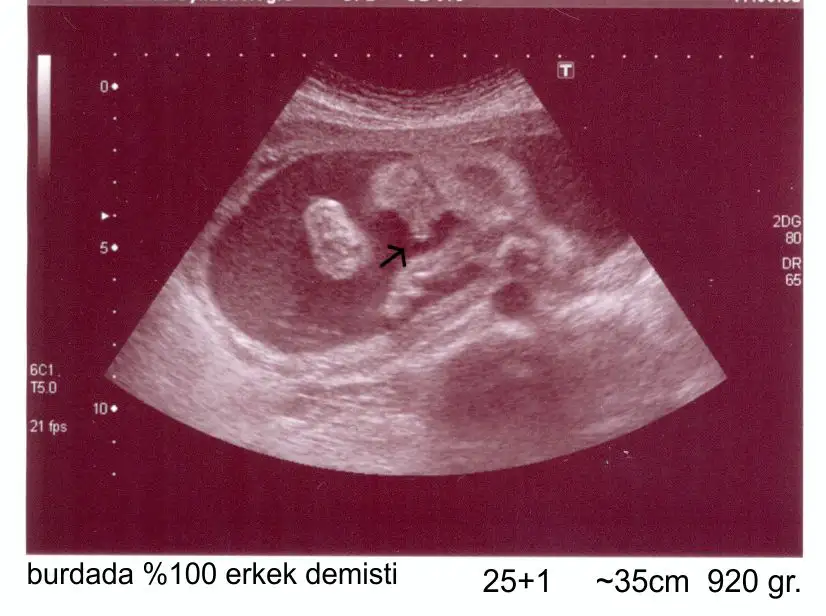

sumruuu cnm bu pipiye benzemiyoki cnm benim,dün gördüm yine ben oğlumun pipisini uyyy kurban olsun annesi oğluşuna.benim usg mi bi koysamda görsen ama bilmiyomki nasıl yükleniyo.

canim valla bilmiyorum iste doktor öyle diyordu ta gecen haftaya kadar. gecen hafta kiz olabilir dedi iste pazartesi gittigim doktorda bana före kiz dedi. hayirlisi olsun canim. sagliklica kucagima alayimda kiz erkek fark etmez. ama sen biliyorsundur yani. pipiye benzemiyo diyorsan ozaman ben kiza iyice bi alisayim. 30 hafta erkege alismistik simdi son 10 hafta kiz beklemek tuhaf. neyse allahim hepimize yavrularimiuzi sag salim kucagimiza almayi nasip etsin.